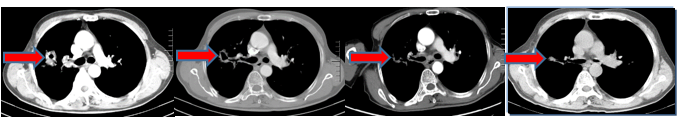

图1 患者免疫治疗前(2017-12)、免疫治疗1个月(2018-04)、12个月(2018-11)、31个月(2020-07)的CT变化情况

2018-01-03至今,予纳武利尤单抗200mg(3mg/kg)Q2w治疗,患者治疗2周期后疼痛逐渐缓解(盐酸羟考酮剂量从140mg逐渐降至20mg),疗效评估为持续PR。患者在免疫治疗期间出现的不良反应为II度甲状腺功能减退,口服甲状腺素片后恢复正常。